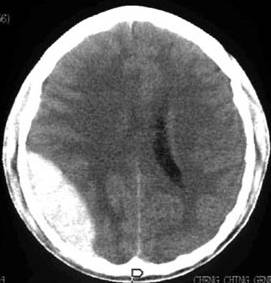

右頂部硬膜外血腫

右頂部硬膜外血腫參考資料